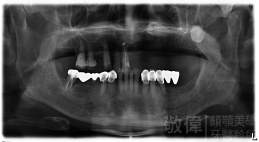

治療前X光   治療後X光